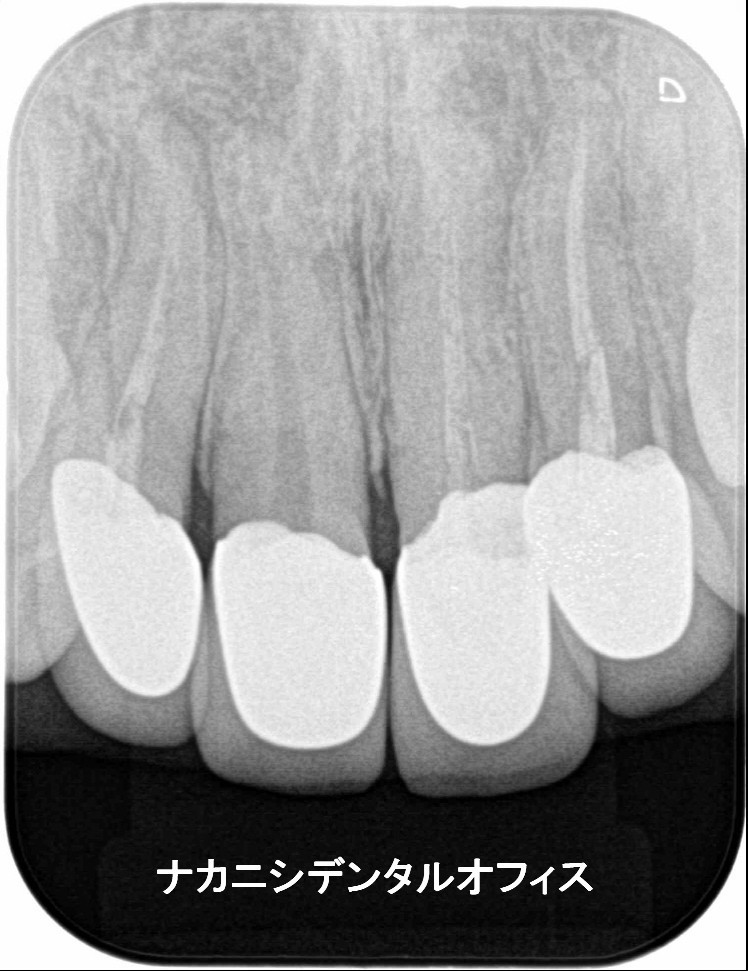

初診時に左上奥歯に冷痛と咬合痛で来院。3年前より、痛みがあったがどこに行っても原因がわからず。マイクロスコープ下で診断したところクラック(ヒビ)がはいっていました。肉眼では確認できず、レントゲンでもわかりませんでした。その日にMTAセメントでクラックを封鎖し経過観察としました。1週間後、冷痛、咬合痛は改善され、神経もとらず温存することができました。

右上の奥歯の痛みと冷水痛で来院されました。かなり神経に近い深い虫歯になっていましたので、年齢や虫歯の状態によりマイクロスコープを使い、MTAセメントで神経の保存を行いました。後日、痛みもしみる感じもなくなり順調に経過をたどっています。